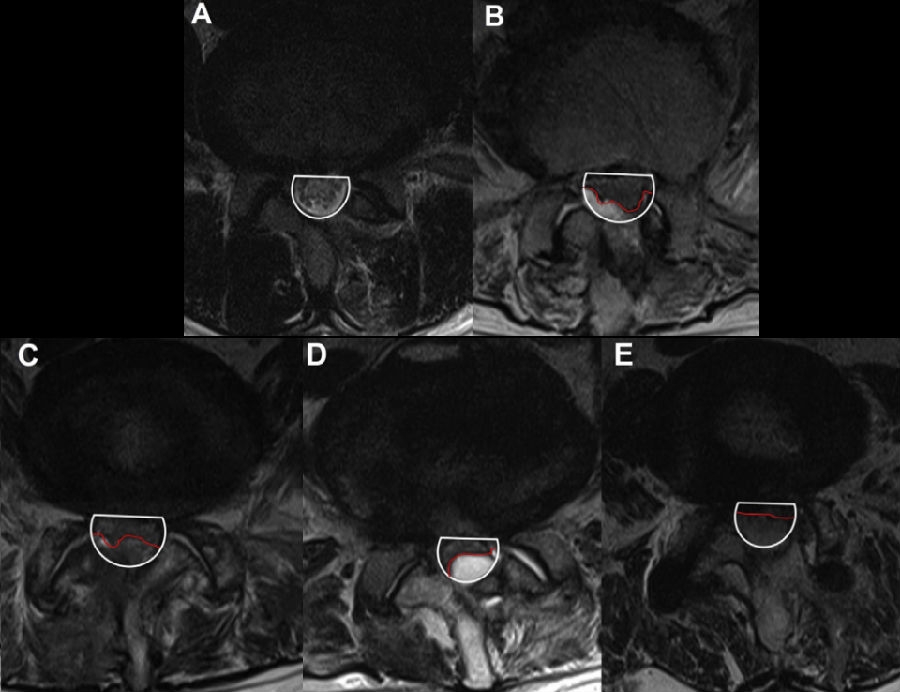

六、复发(2.27%)

病例(椎间盘突出复发)

思考和建议

完整切除突出的椎间盘

切除的椎间盘为影像学体积150%

视情况缝合纤维环,避免复发